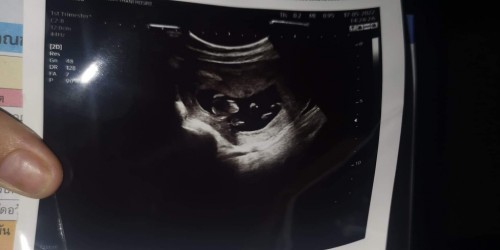

รูปใบอันตร้าซาว

แม่ๆค่ะ ดูออกไหมคะ ทางในรูปมีลักษณะยังไง5555 13+5วีค ##ขอบคุณล่วงหน้านะคะ #ขอบคุณสำหรับคำตอบค่ะ

เหมือนหันข้าง ค่อนไปเกือบเหมือนหันหลังให้ค่ะ